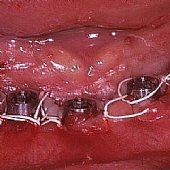

Bilder: Zahnimplantate bei Zahnlosigkeit im Unterkiefer

• Darstellung des Kieferkammes eines zahnlosen Unterkiefers.

• Versorgung mit 5 Implantaten zur Aufnahme der festsitzenden Unterkieferbrücke.